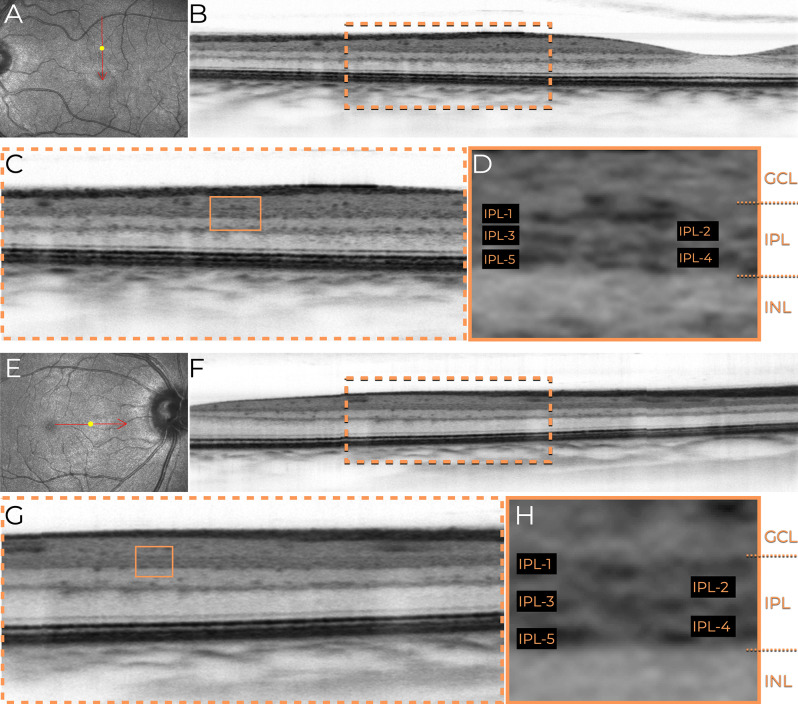

Methods: This retrospective, cross-sectional image analysis study included three healthy individuals who underwent macular OCT imaging. Two subjects were imaged with SD-OCT devices (Nidek RS3000 Advance and Zeiss Cirrus 6000), while one subject was imaged with a swept-source OCT (SS-OCT) device (Topcon Triton DRI). High-density B-scans (1024 A-scans per B-scan) with 120 repetitions for noise reduction were analyzed in both standard and inverted grayscale display modes. The impact of scan size (12 mm, 6 mm, and 3 mm) on IPL visualization was also evaluated.

Results: In conventional grayscale, IPL stratification was indistinct. However, inverted grayscale revealed five IPL sub-bands in all cases, particularly in the parafoveal region where the IPL is thicker. Hyperreflective dots near IPL-1, likely representing the superficial capillary plexus, were also identified. The 3-mm scan protocol provided superior sub-layer differentiation compared to 12-mm scans. However, SS-OCT images did not allow for the distinction of the five IPL strata.